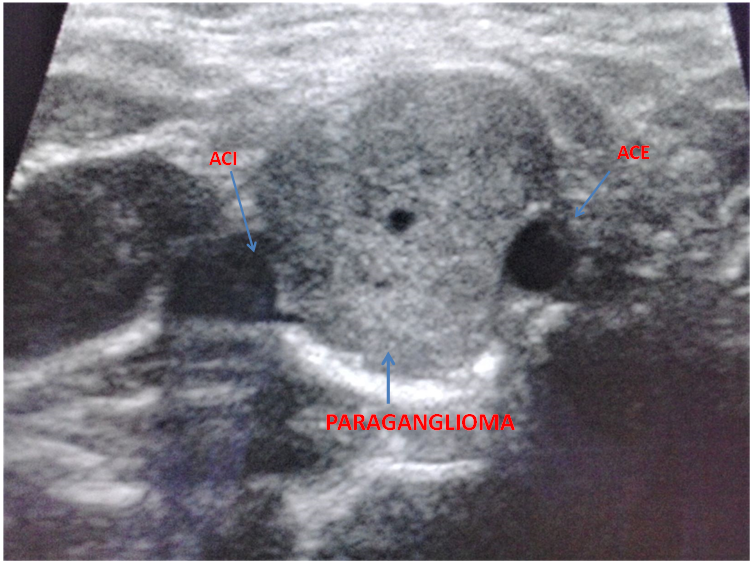

A 31-years old caucasian man came to the neurology emergency department because of the sudden onset of right-sided palsy with sluttered speech. He reported no headache, dizziness or convulsions. After the initial workup, he was admitted to the neurology department. MRI showed subacute ischemic stroke in the posterior part od left insula and operculum. 3D- TOF MR angiography showed occlusion of one of the smaller branches in M2/M3 segment. We performed a doppler ultrasound of carotid and vertebral arteries that indicated vascularized parenchymal structure between ACI and ACE on the right side (Figure 1). Because of that, we did MRI of the neck that verified the inhomogenic structure at the bifurcation of carotid arteries od the right side, dimensions 2,6X1,8X1,9cm that resembles paraganglioma (Figure 2).

Figure 1 Ultrasound of the neck- tansversal plane. Arrows are marking internal carotid artery, external carotid artery and paraganglioma.